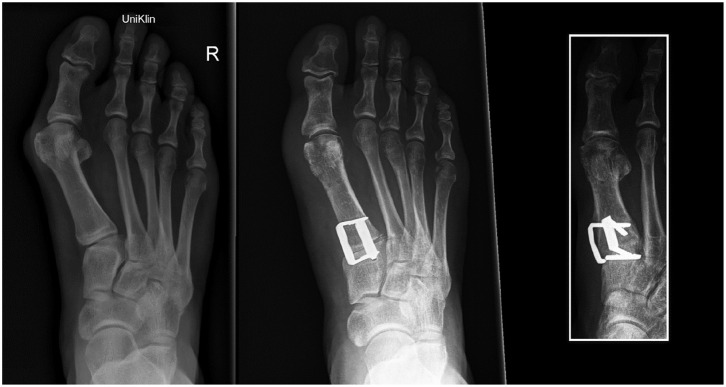

Methods: A total of 60 cases undergoing Lapidus arthrodesis between June 2018 and June 2022 were analyzed with a median follow-up of 37 months (range: 15-64 months). All cases were treated using two nitinol staples (BME EliteTM; DePuy Synthes) for TMT1 fusion. Among these, 38 cases involved additional foot procedures, while 22 cases had isolated TMT1 fusion. Data were collected from medical records, radiographs, and a telephone survey. The hallux valgus angle (HVA) and intermetatarsal angle (IMA) were measured preoperatively and postoperatively on weightbearing dorsoplantar radiographs. Functional outcomes were assessed using the Foot and Ankle Ability Measure-Activities of Daily Living (FAAM-ADL) subscale, and patient satisfaction was evaluated using a 4-point Likert scale.

Results: The TMT1 fusion rate was 96.7% (58/60). The reoperation rate-including hardware removal, revision surgery for recurrence, and nonunion-was 16.7%. The staple breakage rate was 3.3%. The IMA improved from 15.8 to 8.9 degrees (P < .001), and the HVA improved from 37.5 to 17.3 degrees (P < .001). The average FAAM-ADL score was 81.7 out of 84, with 90% of patients reporting being very satisfied or satisfied.